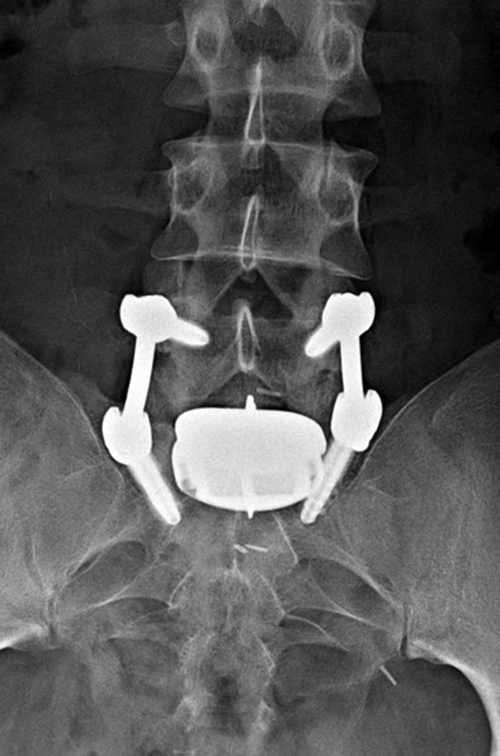

| Anterior lumbar interbody fusion (ALIF) |

Pedicle fixation screws and rods |

| 47 year-old woman with anterior lumbar interbody fusion (ALIF) at L5-S1. |

20 year-old woman with L1 vertebral body compression fracture treated with T12-L2 posterior spinal fusion using pedicle screws at T12 and L2 with connecting rods on each side. |